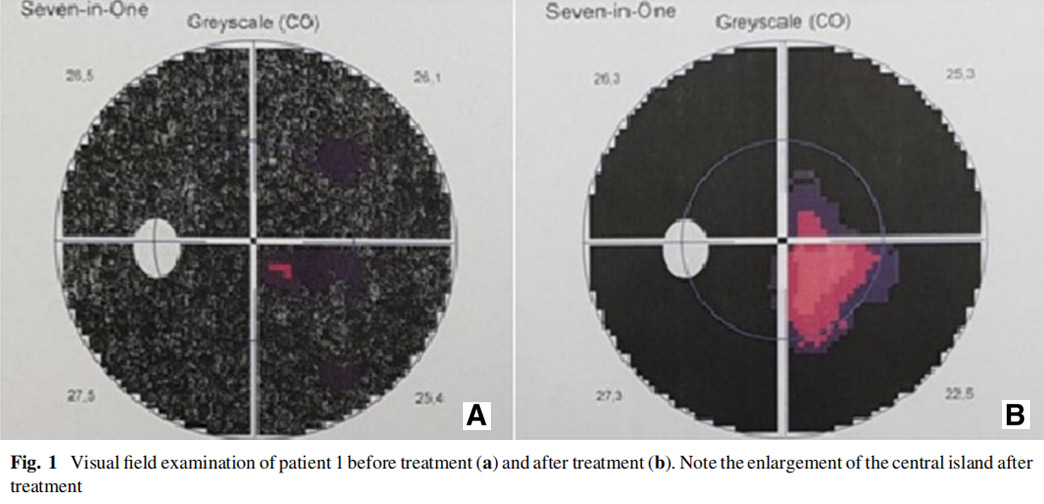

患者1:一名52歲男性,因糖尿病視網膜病變接受了雙側全視網膜氬激光光凝術,在過去2年中一直患有進行性視力喪失,AD-MSCs治療前右眼視力10/200,左眼視力2英尺(約0.6米)處的手部運動(HM),雙眼視神經蒼白,視野檢查顯示雙眼中央島狀結構,左眼較小,mfERG顯示雙眼振幅降低,OCT和RNFL均顯示雙眼黃斑、脈絡膜和神經纖維層變薄。

患者左眼接受AD-MSCs治療,6個月后視力提高至2米處數手指(CF)水平,視野中央島狀結構擴大,如圖1所示,左眼mfERG顯示改善(圖2),脈絡膜厚度從273μm增加至318μm(圖3),黃斑厚度和RNFL沒有變化。